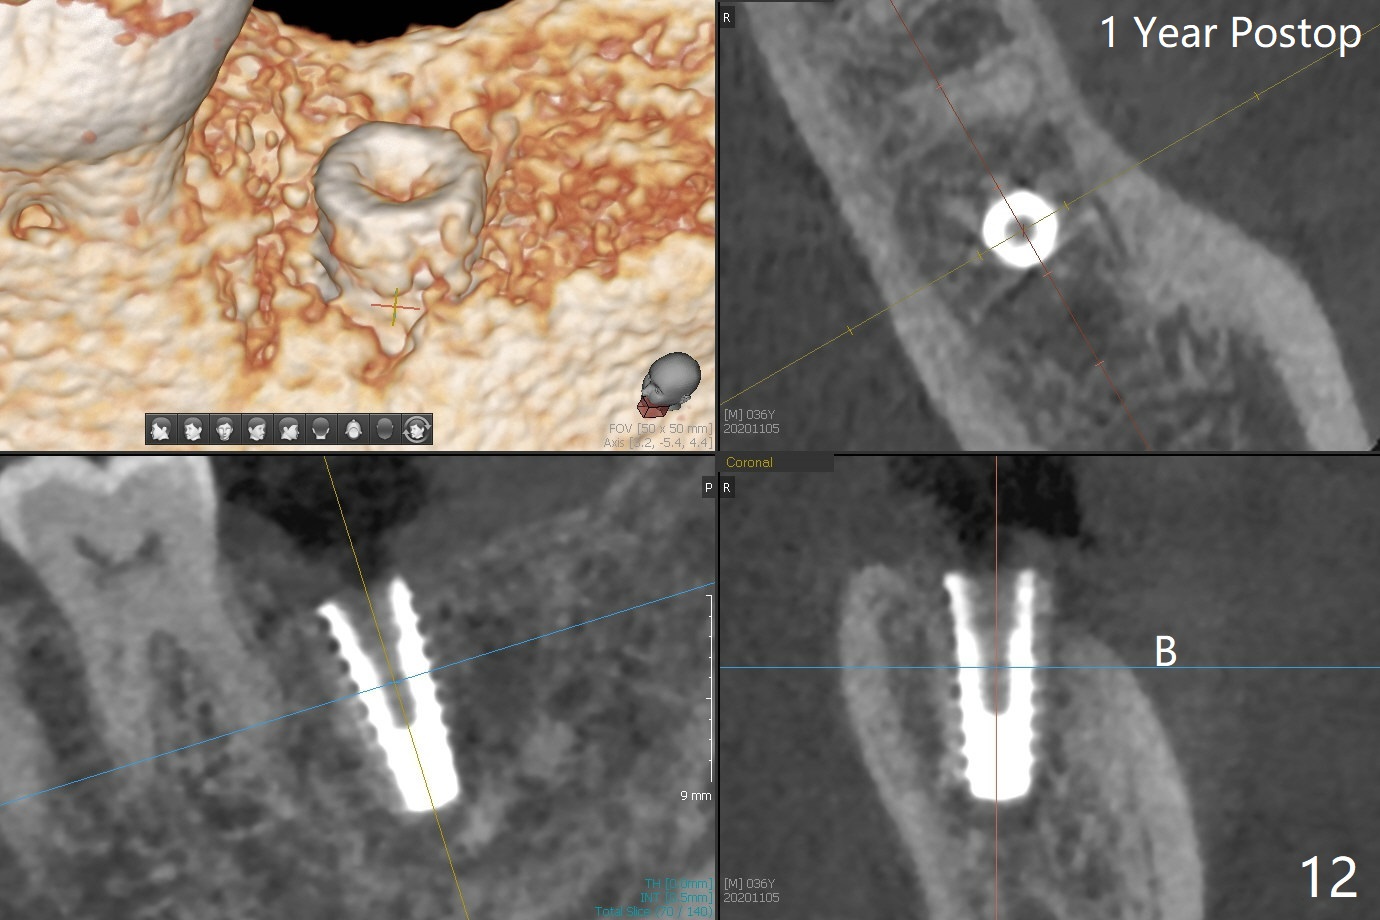

After placement of a 5x11 mm implant and cover screw at #18, allograft mixed with PRF (sticky bone) is placed in the peri-implant space, but it appears that bone density in the apical region (Fig.1 A) is lower than that in the coronal one (C) because of a constriction between the implant and the distal crest (*). Ideally the undercuts (Fig.2 *) of the extraction socket (black area) should be identified. Place bone graft in the undercuts (Fig.3 red circles) after osteotomy (white outlines) and before implant placement! A 4.5x1 mm temporary abutment is placed for an immediate provisional. The 2nd shortcoming of this case is that the implant is placed a little buccal. The papilla mesial to the immediate provisional (Fig.4 P) looks normal 4 days postop (no food impaction is expected when a final restoration is cemented). Additional acrylic (*) was placed to close a buccal gap when the provisional was seated with the temporary abutment. The patient reports loss of a piece of material in 4 days. It must be the additional acrylic, since it is absent 6 weeks postop (Fig.5). The provisional (Fig.5 P) looks wide, probably related to post-extraction gingiva and bone atrophy (Fig.6, 7 *). Bone graft (Fig.6 <) becomes a component of the gingival cuff. The provisional is re-trimmed for better oral hygiene. The gingival cuff is basically healthy 3.5 months postop, although the temporary abutment is loose and the implant is tender to rewinding and winding (Fig.8). The implant seems to remain non-osteointegrated 3.5 months postop (Fig.9). Although the bone density around the implant increases nearly 6 months postop (Fig.10), the implant remains tender when a 5x4(4) mm pair abutment is tightened. The healing abutment is reused. The bone density around the implant increases 11 months postop (Fig.11). Uncover is done with 5.5 mm profile drill. One month post uncover (12 months postop), the implant remains unstable (Fig.12). Prepare sticky bone x1. Make incision for exploration, including retightening the implant after Titanium brush and H2O2 Q-tip rubbing. If needed, a larger and shorter UF implant is a replacement (Fig.13). The implant is removed, cleaned with Titanium brushes and H2O2 in vitro and repositioned 12 months postop (Fig.14: arrow (gaps: post granulation tissue removal)). The gaps are regrafted with sticky bone and covered with PRF membrane and Cytoplast. Although the patient complains of severe pain the first 2-3 postop, the wound is apparently healing 12 days postop. The Cytoplast is exposed asymptomatic 5 weeks postop (Fig.16) and removed (Fig.17). The wound appears to have healed without loss of the bone graft (Fig.18).术后四个月伤口愈合,骨粉几乎没有丢失,有骨小梁形态(图十九:*)。切开,刮匙去骨,有一定硬度,即刻放置修复基台,完全就位(图二十),制备临时牙冠,牙周敷料固定组织瓣(没有缝线)。